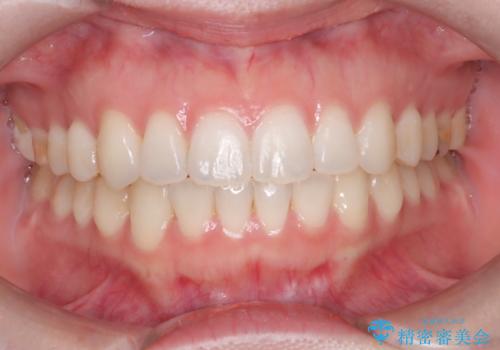

治療中は咬合バランスや歯列の中心(正中)の位置にも注意を払い、最終的には上下の正中が一致し、左右の臼歯関係も理想的な形に改善されました。見た目の変化はもちろん、かみ合わせの安定や清掃のしやすさも向上。

患者さんからは「笑ったときの印象が大きく変わって嬉しい」「しっかり噛めるようになった」との感想をいただきました。現在は保定装置で後戻りを防ぎながら、良好な状態を維持しています。